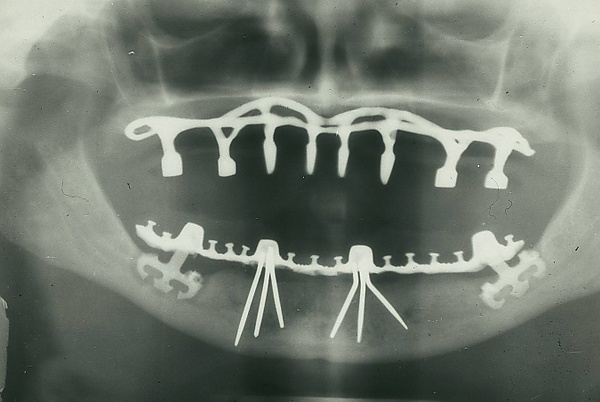

В настоящее время стоматология шагнула далеко вперёд. Стала возможной имплантация зубов и восстановление даже очень сильно разрушенного зуба, появились качественные пломбировочные материалы и современные инструменты для лечения зубов. При этом имплантация зубов возможна как при единичной потере зуба, так и при полном их отсутствии, для этого используют технологию вживления искусственного корня в костную ткань челюсти — зубных имплантатов, что даёт возможность восстановить сегменты зубного ряда зубными имплантатами без нарушения целостности и функциональности рядом стоящих здоровых зубов.

Ортопедическая стоматология

Эстетическая стоматология широко применяет весь существующий инструментарий для создания безупречной белоснежной улыбки — брекеты в их разнообразии (для исправления прикуса), вкладки и виниры (для корректировки формы и цвета).